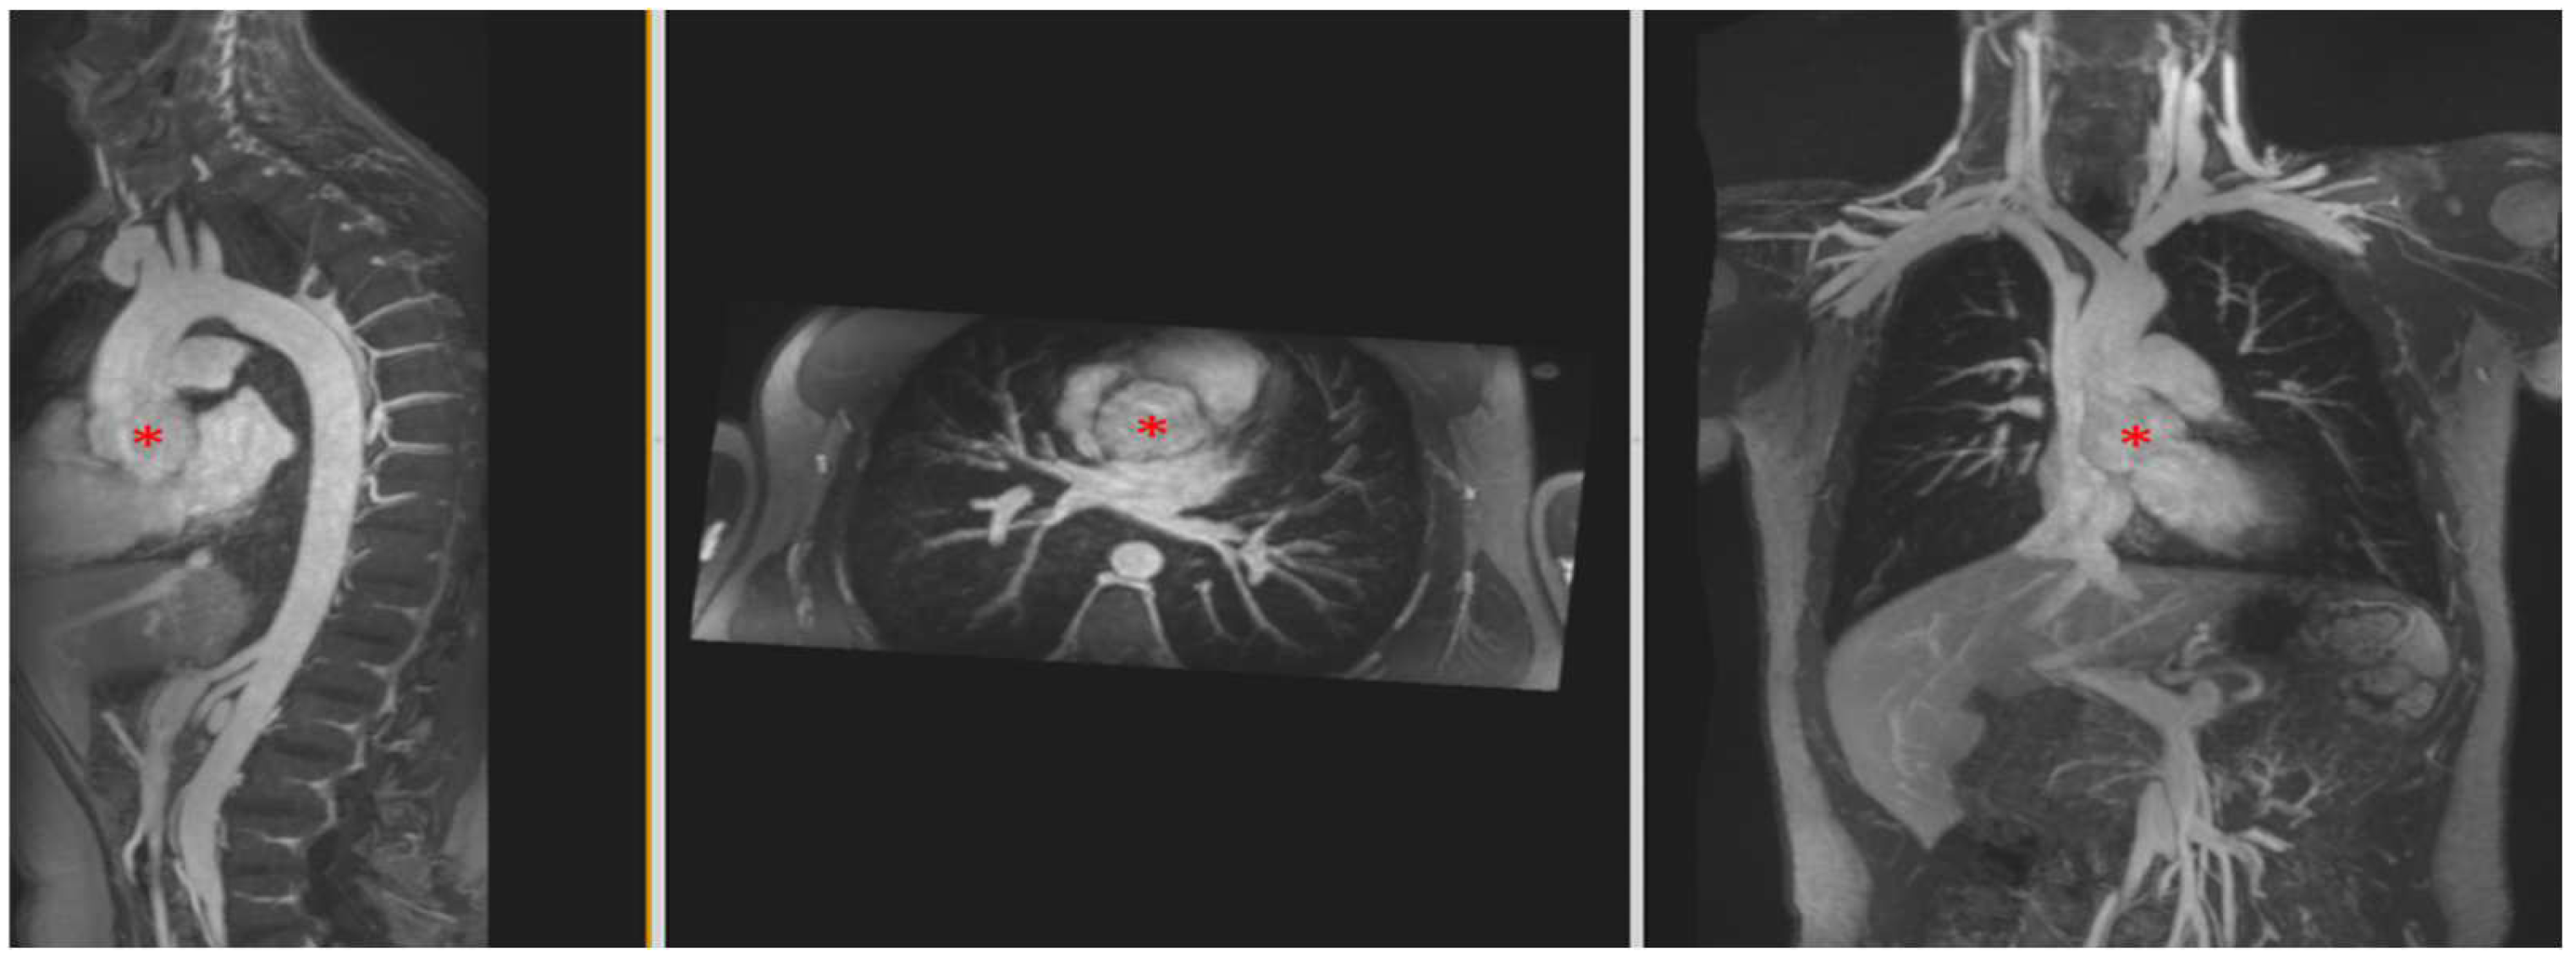

4.3.2. Aortic Aneurysm in Connective Tissue Disease

| Aortic Aneurysm | Genetic syndromes linked to aortic aneurysms and dissection include (among others): Marfan’s, Loeys–Dietz, vascular Ehlers–Danlos, and Turner’s. Bicuspid aortic valve also confers a higher risk. High-resolution imaging of the entire aorta and its branches can be readily achieved with FE steady-state imaging. |